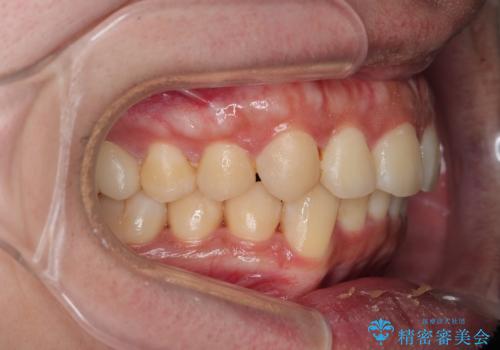

がたつきが気になる。インビザラインでスッキリ。

- インビザラインモデレート

- 奥歯の噛み合わせは特に問題ないため臼歯を特に大きく動かす事はなく。

歯と歯の間を削る(ディスキング)、拡大を行いマウスピースで矯正を行いました。

がたつきもなくなりスッキリした歯並びになりました。

がたつきが無くなると歯ブラシがしやすくなり汚れが溜まりにくい口腔環境ができます。